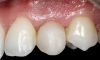

(30.) Smile, retracted, and close-up views of the provisional restoration at the 4-month follow-up appointment to assess the development of tissue volume and contours. Note that most of the open gingival embrasures have filled with papillae and that the gingival zenith exhibits excessive volume.

Figure 30

(31.) Smile, retracted, and close-up views of the provisional restoration at the 4-month follow-up appointment to assess the development of tissue volume and contours. Note that most of the open gingival embrasures have filled with papillae and that the gingival zenith exhibits excessive volume.

Figure 31

(32.) Smile, retracted, and close-up views of the provisional restoration at the 4-month follow-up appointment to assess the development of tissue volume and contours. Note that most of the open gingival embrasures have filled with papillae and that the gingival zenith exhibits excessive volume.

Figure 32